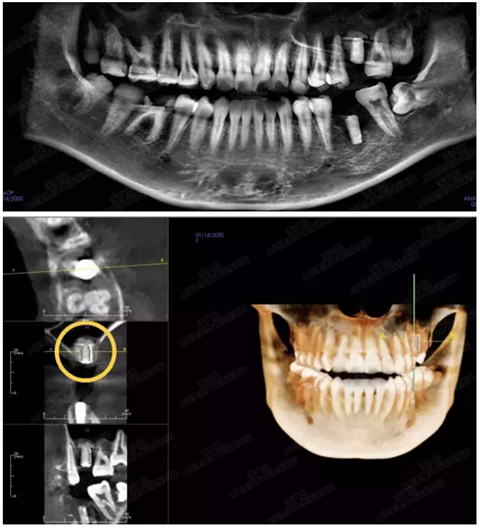

病例二

剩余骨量2mm

003.png

提升10mm

004.png